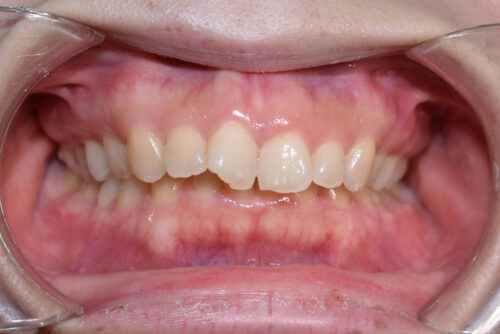

初診時年齢 30歳 女性

過蓋咬合と

叢生(歯ならびの デコボコ)

を主訴に

池袋よりひとつ隣駅の東京都豊島区大塚駅すぐの大塚たまみ矯正歯科へ

いらっしゃいました。

下の歯が 全く見えない状態で

上下の歯が 翼のように ガタついて(翼状捻転)いる

状態でした。

ワイヤー矯正治療10か月後です。